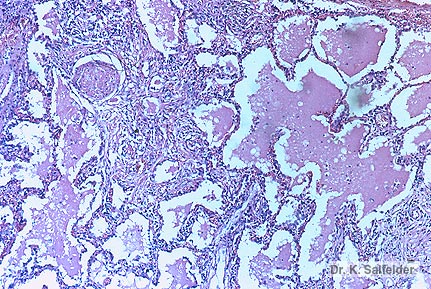

Abb. 9,29: Histoplasmose

Bei der akuten Infektion der Lungen kann es zu einer diffusen oder lokalen lipo-proteinaeren Alveolarreaktion kommen. HE-Faerbung